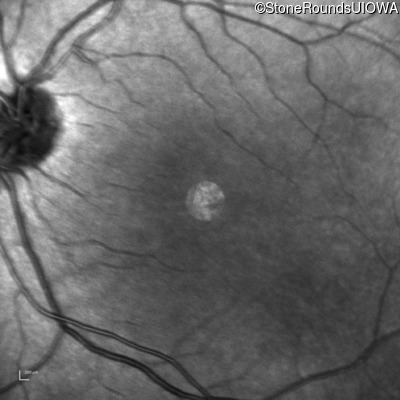

Infrared Fundus Photograph - Right - 10/200

Exemplar

Infrared Fundus Photograph - Left - 10/100